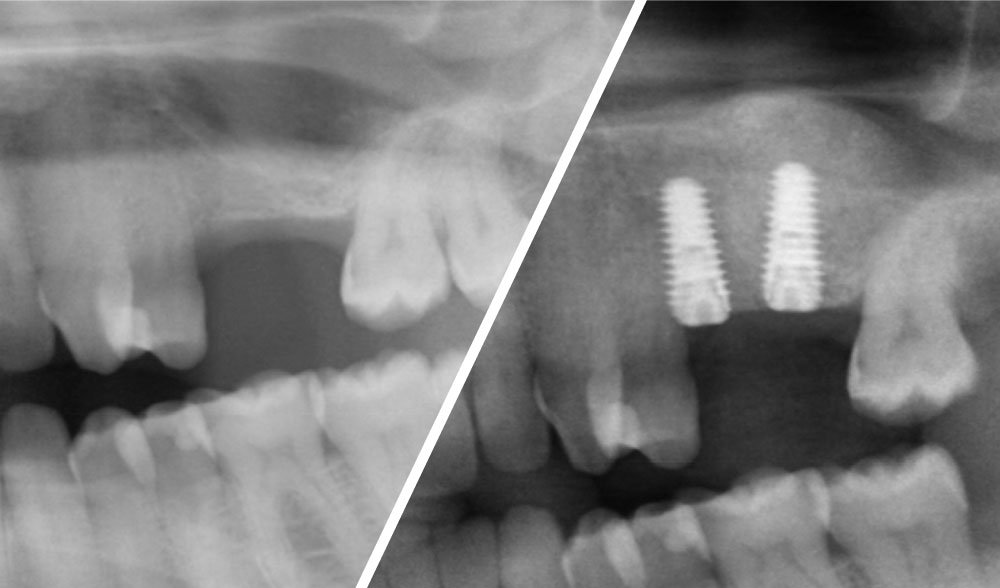

Fractured implants in the mandible

Fractured implants; removal of the implants, ridge reconstruction with Lamina®, MP3® and autogenous bone and placement of 2 new ExFeel implants after 4 months healing period.